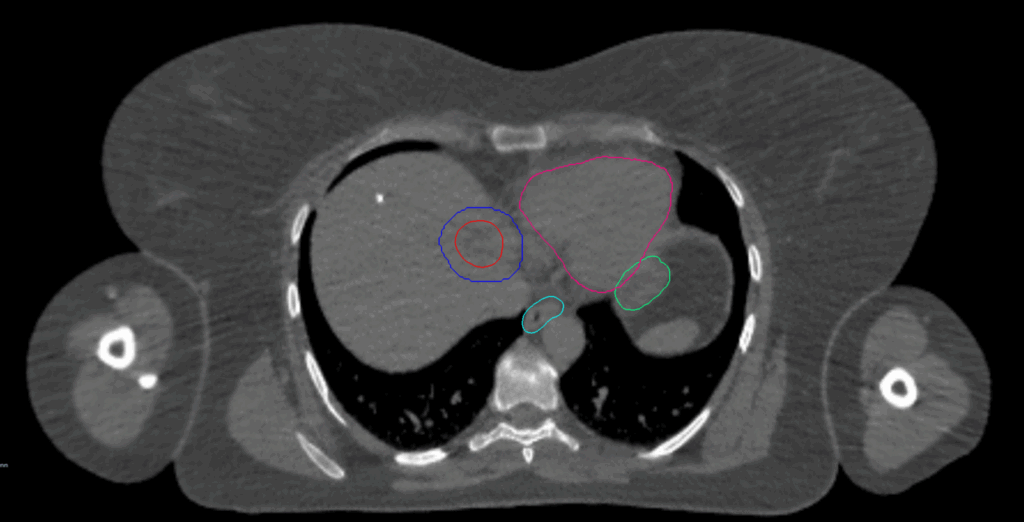

Planning CT Images

Follow-up PET-CT: solitary hypermetabolic lesion in the liver, measuring 2.9cm with no other lesion